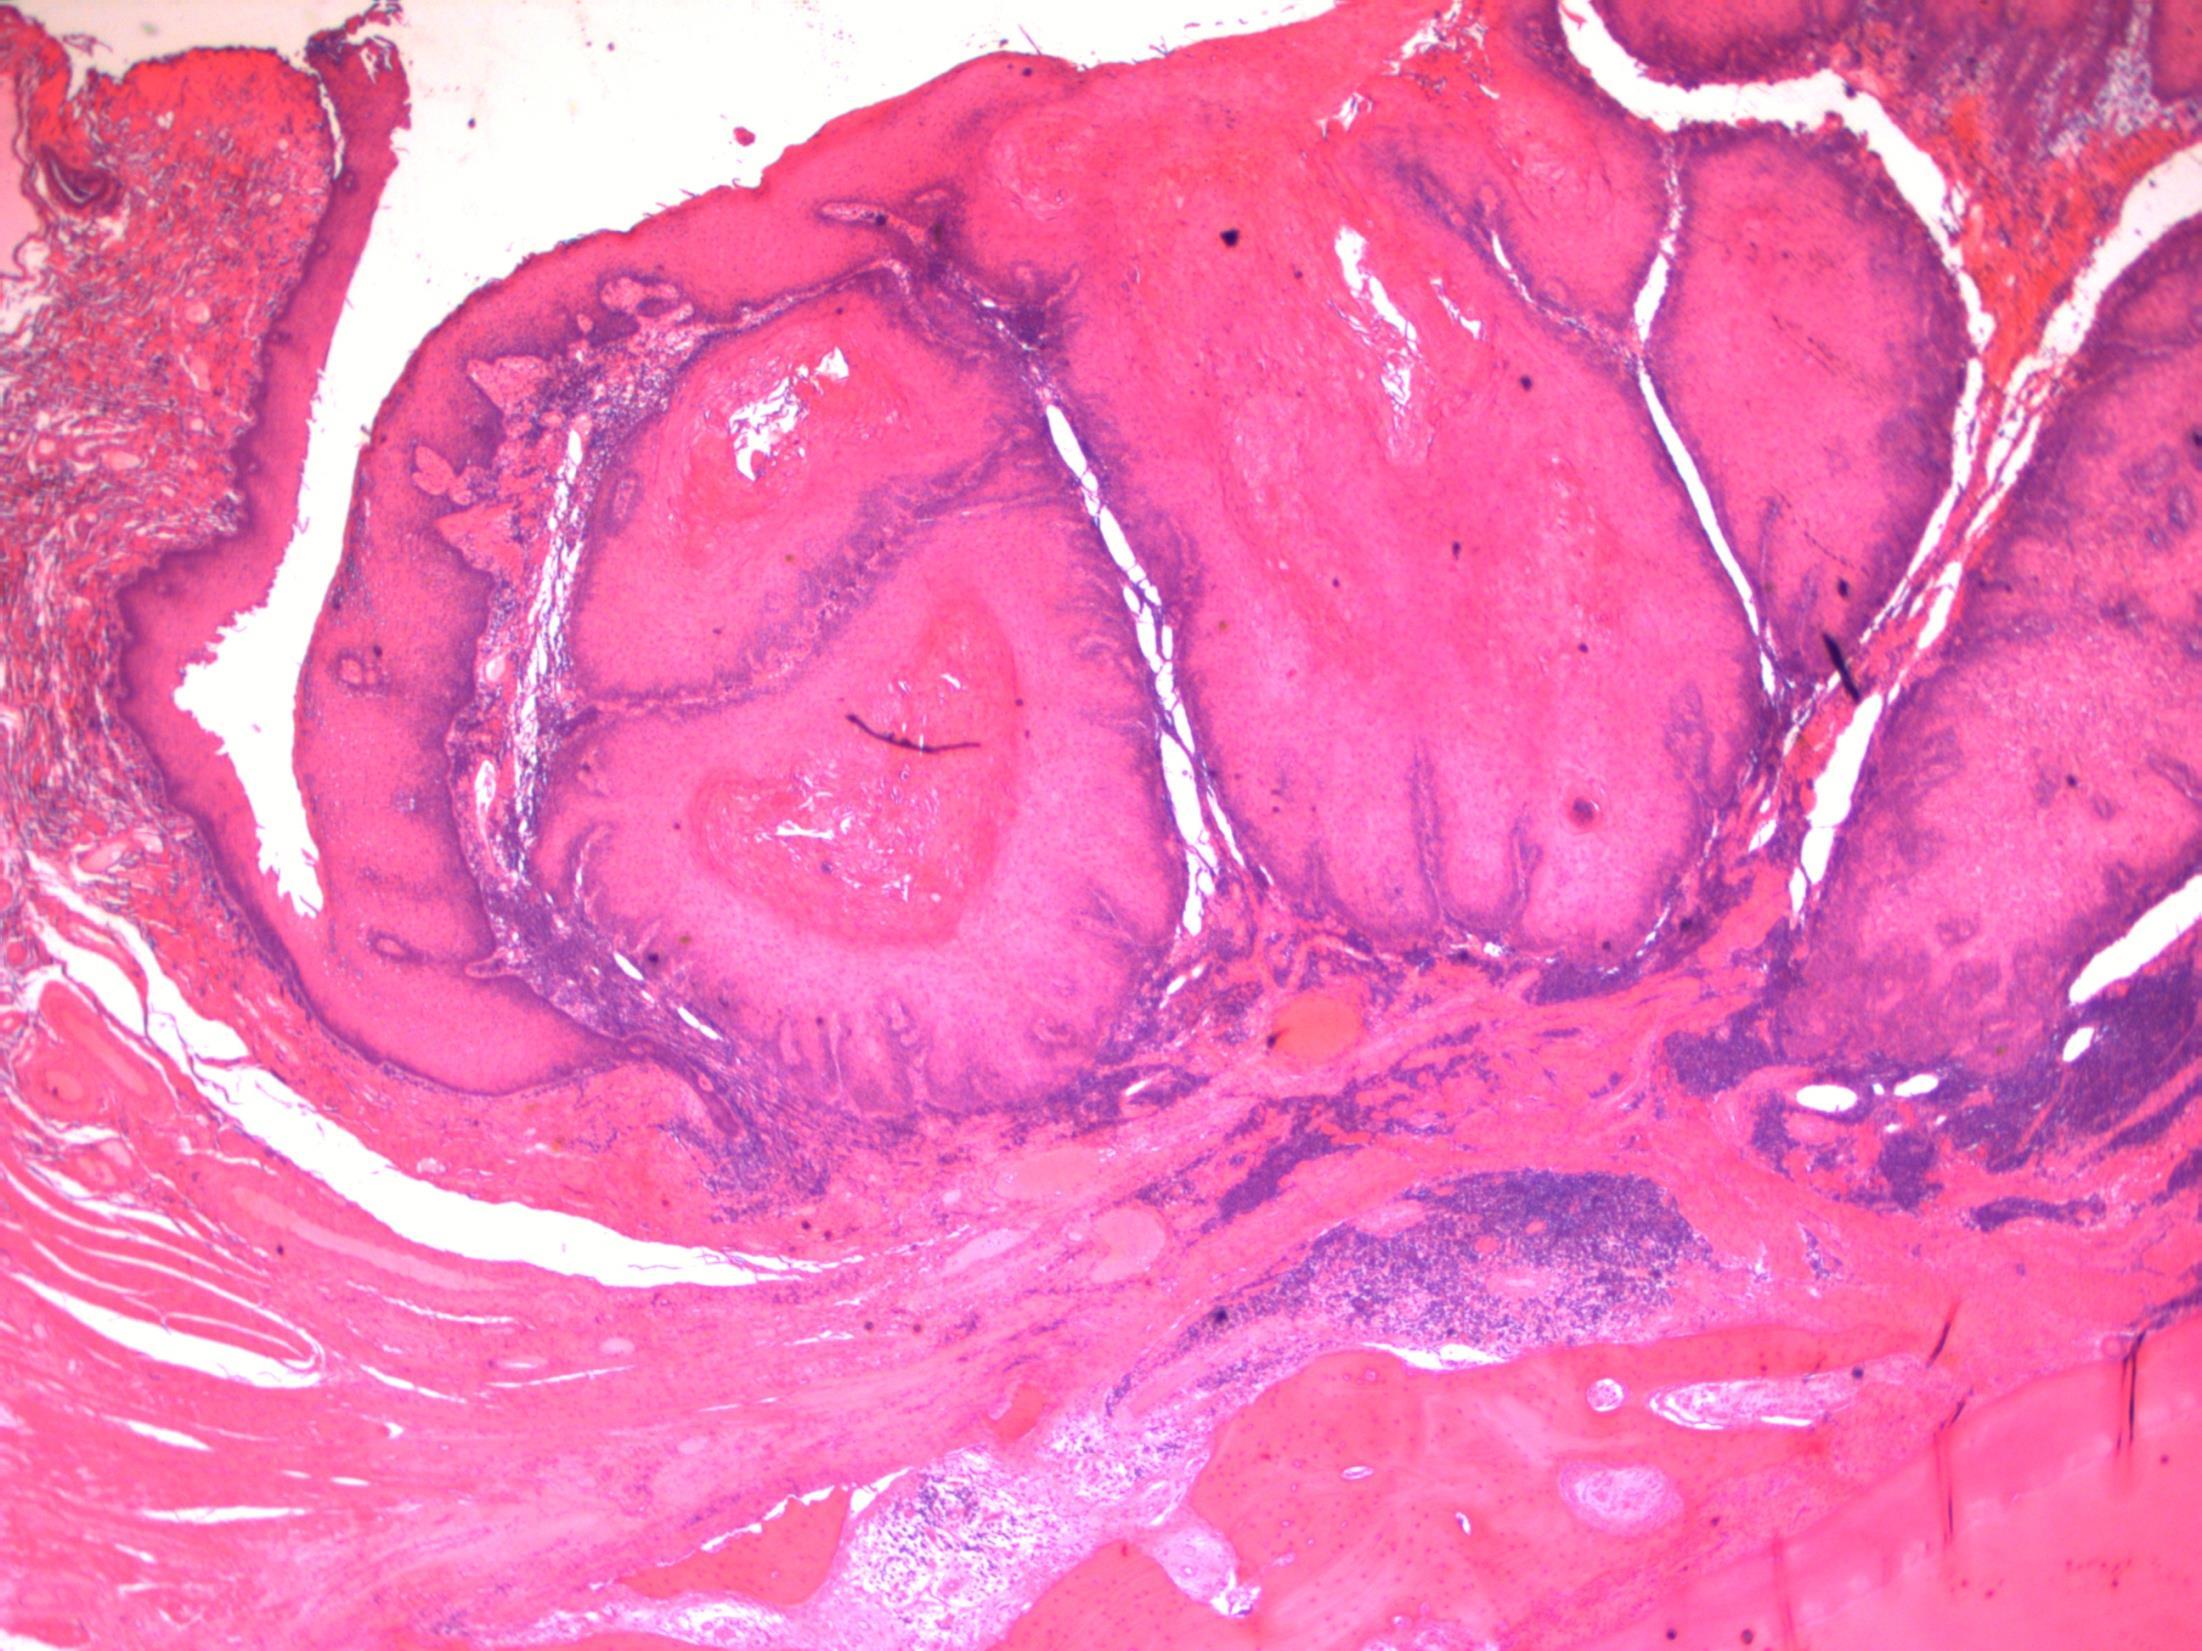

Verrucous carcinoma

Description: Abrupt transition between tumour and epithelium. Plump papillary invaginations of thickened and infolding epithelium, hyperkeratosis. Lack of cytological atypia, suprabasal mitoses. Retraction of normal epithelium at margin. Diagnosis: Verrucous carcinoma Differential Diagnosis:

Conventional SCC – cellular atypia • Squamous papilloma – more exophtyic & branching, less keratin • Reactive inflammatory epithelial hyperplasia – most difficult but rete pegs more slender and anastomosing; no mitoses; macro correlation Plan: Correlate with previous biopsies ( often quite bland so can be inconlusive) Examine further blocks for worse areas and measure margins. Comments: In head and neck – oral cavity and larynx Often large, locally aggressive, pushing margin Better prognosis than SCC

3.5 Clinical features 3.0 Potential differential diagnosis with justification (correlate history too) 2.5 Description with diagnosis 2.0 Differential diagnosis with mention of verrucous carcinoma 1.5 Uncertain, but some mention of ‘atypia’ 1.0 Benign diagnosis Case 19